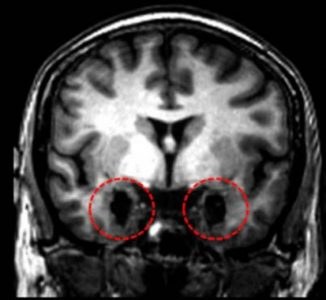

Etape 1 : Comparaison de l'IRM anatomique cérébrale de la femme sans peur avec une IRM saine afin de mettre en évidence une éventuelle lésion

Les cercles rouges localisent les amygdales (zone de substance grise) chez un sujet sain. Chez la patiente SM (cercles en pointillés rouges), les amygdales sont lésées de façon bilatérale.

- Pour réaliser la comparaison rendu délicate par l'impossibilité d'explorer le cerveau de Mme SM et la présence d'un seul plan de coupe, les structures anatomiques indiquées en vert doivent servir de point de référence pour obtenir avec EduAnat2 un plan de coupe similaire à celui de la photo. - les 2 ventricules latéraux (VL) - le troisième ventricule (V3) - le noyau caudé (NC) correspondant à de la substance grise - Travail dans le plan coronal uniquement avec EduAnat2 car nous ne disposons pas de l'image IRM de la patiente SM, mais seulement d'une image dans le plan coronal.